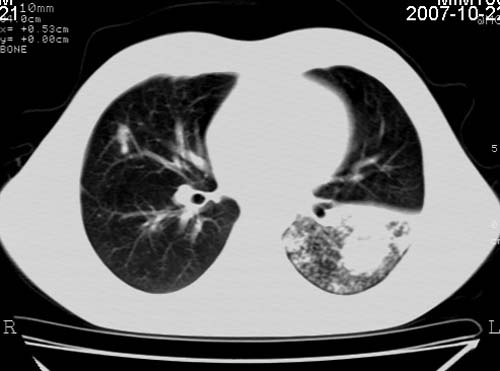

男,21岁,咳嗽、胸闷、乏力伴多汗二十余日、无明显发烧。患者一般情况好,为初三学生。

右肺上叶前段及左肺下叶多形性病变伴厚壁空洞,周边示树芽征.左肺下叶不张改变.

考虑;肺结核,不除外左肺下叶支气管内膜结核.

双肺继发性肺结核伴左侧空洞形成!不除外合并霉菌感染!(双肺多发病灶,左侧病灶形成空洞,并空洞内见壁结节。建议改变体位,观察空洞内结节情况,以便排除霉菌感染!)